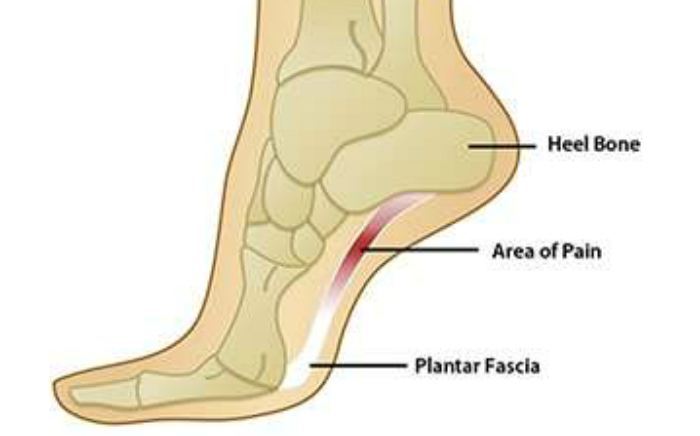

Common Foot & Ankle Disorders

Did you know the foot has 26 bones, 33 joints, 107 ligaments, 19 muscles, and numerous tendons? These parts all work together to allow the foot to move in a variety of ways while balancing your weight and propelling you forward or backward on even or uneven surfaces. It is no wonder that 75 percent of all Americans will experience foot problems at one point or another in their lifetimes.